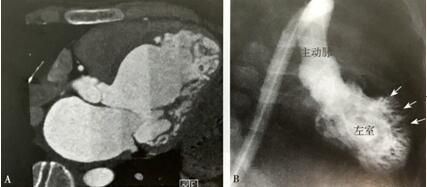

心脏CT在2001年开始应用于LVNC的诊断,并认为可以清晰显示左心室非致密心肌层的结构(图6A)。2007年以来有增多的趋势,但因放射线辐射有导致肿瘤的风险,尤其对儿童及需长期随诊的患者,不提倡CT诊断。左心室造影可以明确显示心肌肌小梁,但因有创性检查故不作为诊断手段(图6B)。

图6 CT和造影显示异常的肌小梁 LVNC的CT图像显示异常肌小梁;B.左心室造影图像显示异常肌小梁